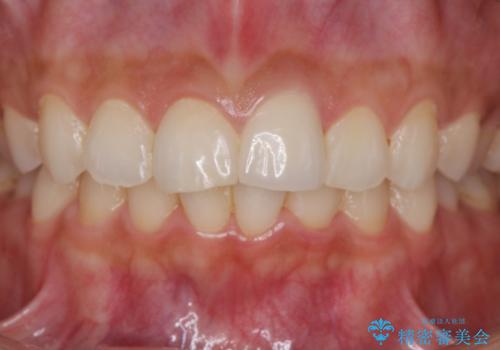

すり減った前歯の形態回復

- すり減ってしまった前歯の審美性の回復を希望され来院されました。

何度かレジン修復を試みたものの、脱離しやすく変色も気になる、とのことでセラミッククラウンによる審美性の回復を計画します。

右側は、クラウンにせず可及的に形態を整えることのみでの対応としました。

自然な色調のセラミッククラウンで審美性を回復することができ、大変満足いただけました。